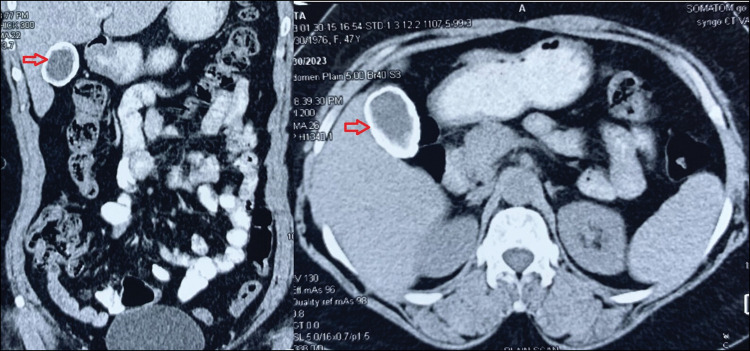

Commonly referred to as a "porcelain gallbladder (PGB)," gallbladder calcification is usually asymptomatic. It is observed that chronic inflammation of the gallbladder can occur as a result of another underlying condition, specifically gallstone disease. In the past, there was a belief that PGB had a correlation with gallbladder cancer, with an incidence rate of 30%. However, recent studies have indicated that the rate is only 5%-22%. Patients diagnosed with PGB, who are deemed to be at an elevated risk of developing cancer may undergo prophylactic cholecystectomies. However, recent research indicates that a subset of these patients may potentially avoid this surgical intervention. As a result of the increased risk of gallbladder cancer, and the difficulty of holding and retracting the gallbladder, laparoscopic cholecystectomy was not often recommended for patients with PGBs in the past. However, with the advancement of technology laparoscopy is now a choice for such difficult cases. Here we report a case of PGB in a 55-year-old female patient who complained of intermittent pain in the right upper abdomen with vaginal discharge. She was successfully managed laparoscopically.